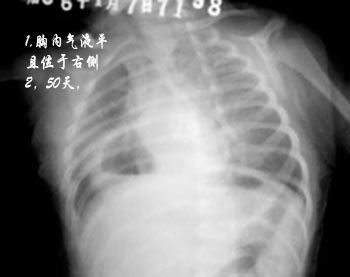

本例应为先天性食管裂孔疝。

如下图所示,由于卧位气影的衬托,可以看出病由。

病人体位略不正,膈上纵隔右胸腔内带可见一气囊影,下部示气液平面,囊壁较光整,与肺界面清晰,其左下角与胃泡关系密切,胃泡内气体较少,支持膈疝。

右侧肋骨上抬,右侧胸腔见空泡内有液平,其壁似与下方肠管连续,考虑膈疝吧。